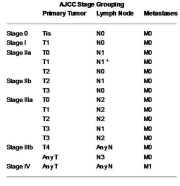

| 11:55, 7 בספטמבר 2012 | TNM123.png (קובץ) |  |

51 קילו־בייטים | Motyk | 1 | |